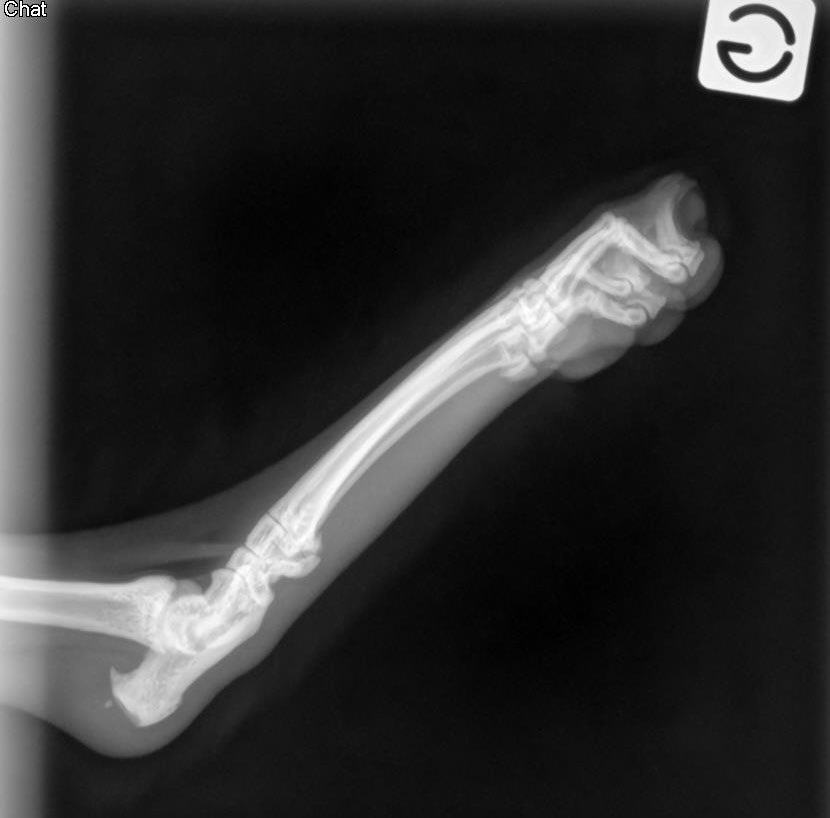

J’ai un chat qui boite mais sans plaie sur la patte arrière gauche. Est ce qu’une âme charitable peut me dire si elle voit qqchose sur les radio ? #vetotoctoc Elle est sous Bioclamox et Metacam car personne ne sait ce qu’il se passe. 🫶 merci